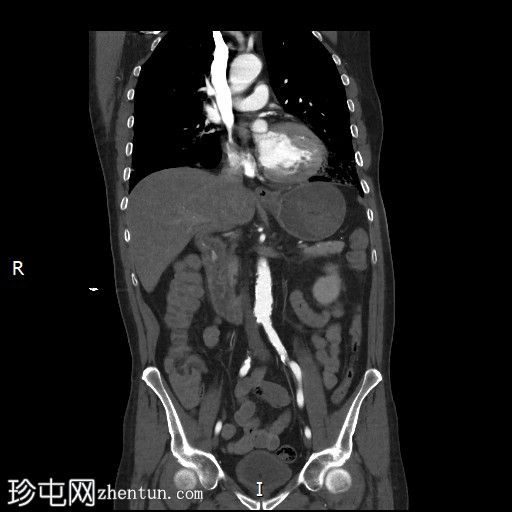

冠状位增强扫描

动脉期

胃内出血

造影剂外渗提示十二指肠第二段活动性出血